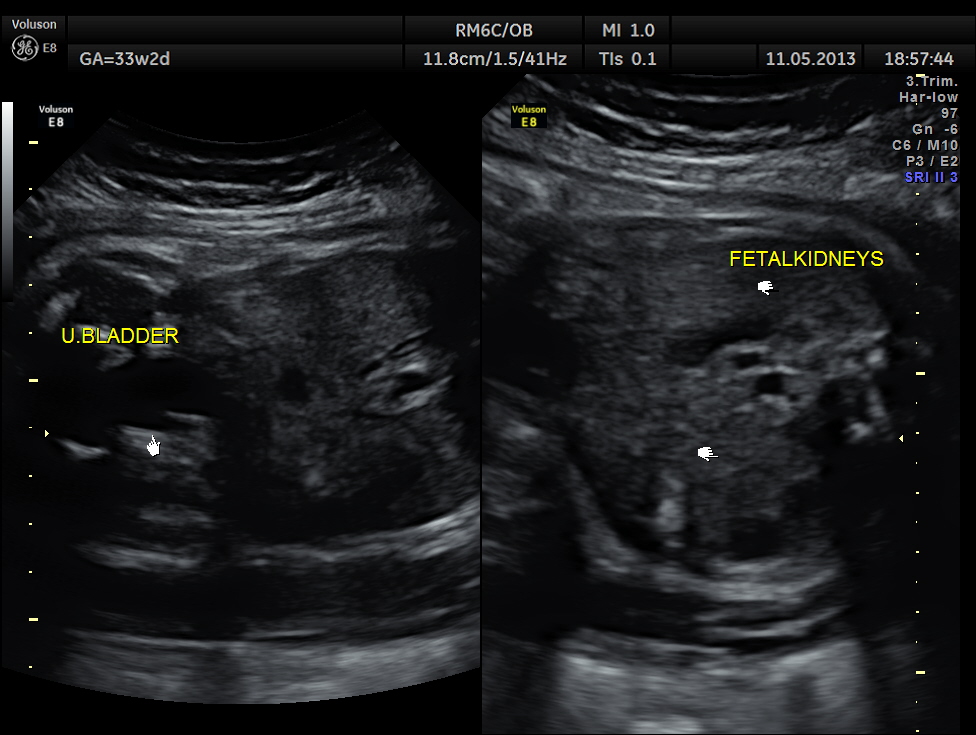

https://kriznanultrasoundimages.com/2013/05/12/tetralogy-of-fallot-tof/ at this time there was a revision of the cardiac findings : LEFT ATRIAL ISOMERISM WITH TETRALOGY OF FALLOT The irregular rhythm was not made out now. Apart from this the foetus has symmetrical IUGR and oligohydramnios Now the child was brought when she was 51 days old . She was born prematurely at 33 weeks of gestation . She had been seen at three higher institutions . The paediatric cardiologist has given a working diagnosis of CONO TRUNCAL VSD. But the catch was that the child had renal dysfunction with s .creatinine around 2 mgms and the ultrasound could not visualise the left kidney. The right kidney was reported to be hyperechoic . The following 2 pictures were of the fetal kidneys , as seen during the scan earlier.

The following two pictures show the hyperechoic kidneys of the child with mild pelvi calyceal dilatation . The kidneys were picked up only with the 11 mhz transducer.